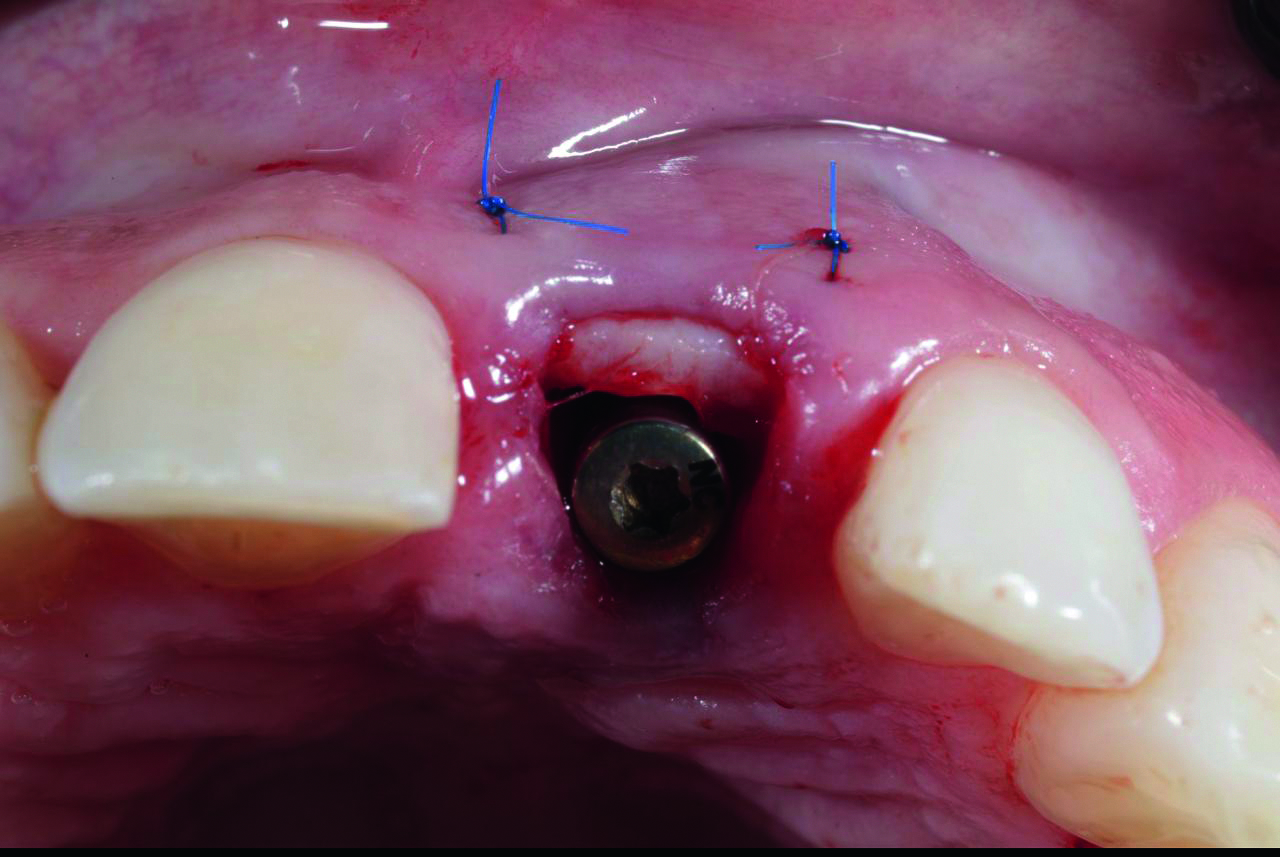

• Пластика мягких тканей в области имплантатов